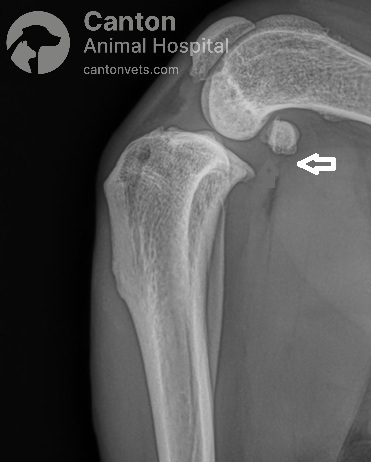

Radiographs (X-rays)

Used to rule out other causes of lameness.

Common findings in chronic or partial CCL tears:

Fat pad compression (“fat pad sign”) and joint capsule swelling due to fluid buildup.

Osteophyte (bone spur) formation on the trochlear ridge, tibial plateau, and patella.

Thickening of the fibrous joint capsule and subchondral sclerosis (increased bone density).

Radiographs (X-rays) – The fat pad sign and presence of osteophytes (bone spurs) indicate possible CCL damage.

Tibial Plateau Leveling Osteotomy (TPLO) is a precise orthopedic procedure that requires detailed preoperative planning to achieve the best results. Before surgery, radiographs (X-rays) are taken to measure the dog's tibial plateau angle (TPA) and calculate the necessary rotation to achieve an optimal final angle of 5 to 6.5 degrees.